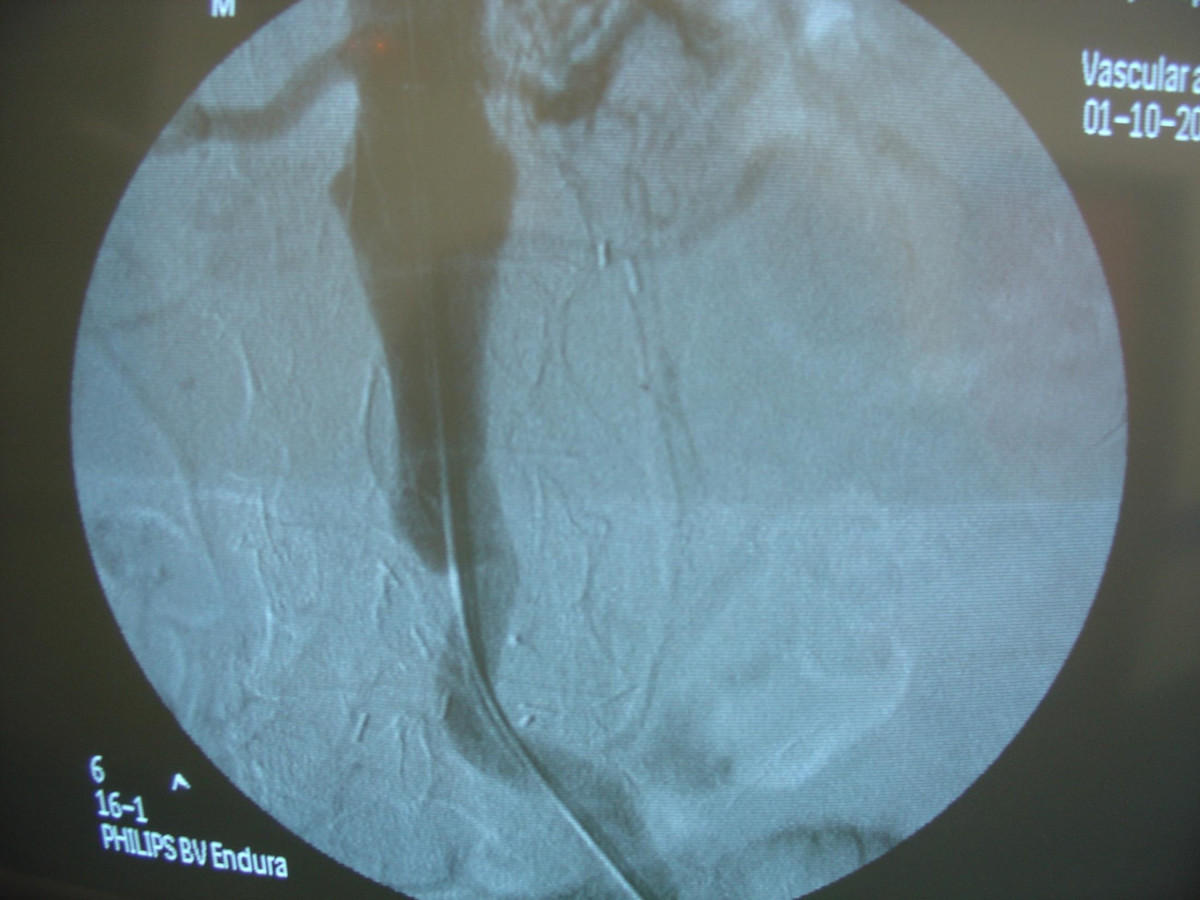

Endovascular repair of anastomotic abdominal aortic aneurysm, after aortobifemoral bypass

Vascular Clinic, Naval and Veterans Hospital of Athens

AVEM2009-Thessaloniki